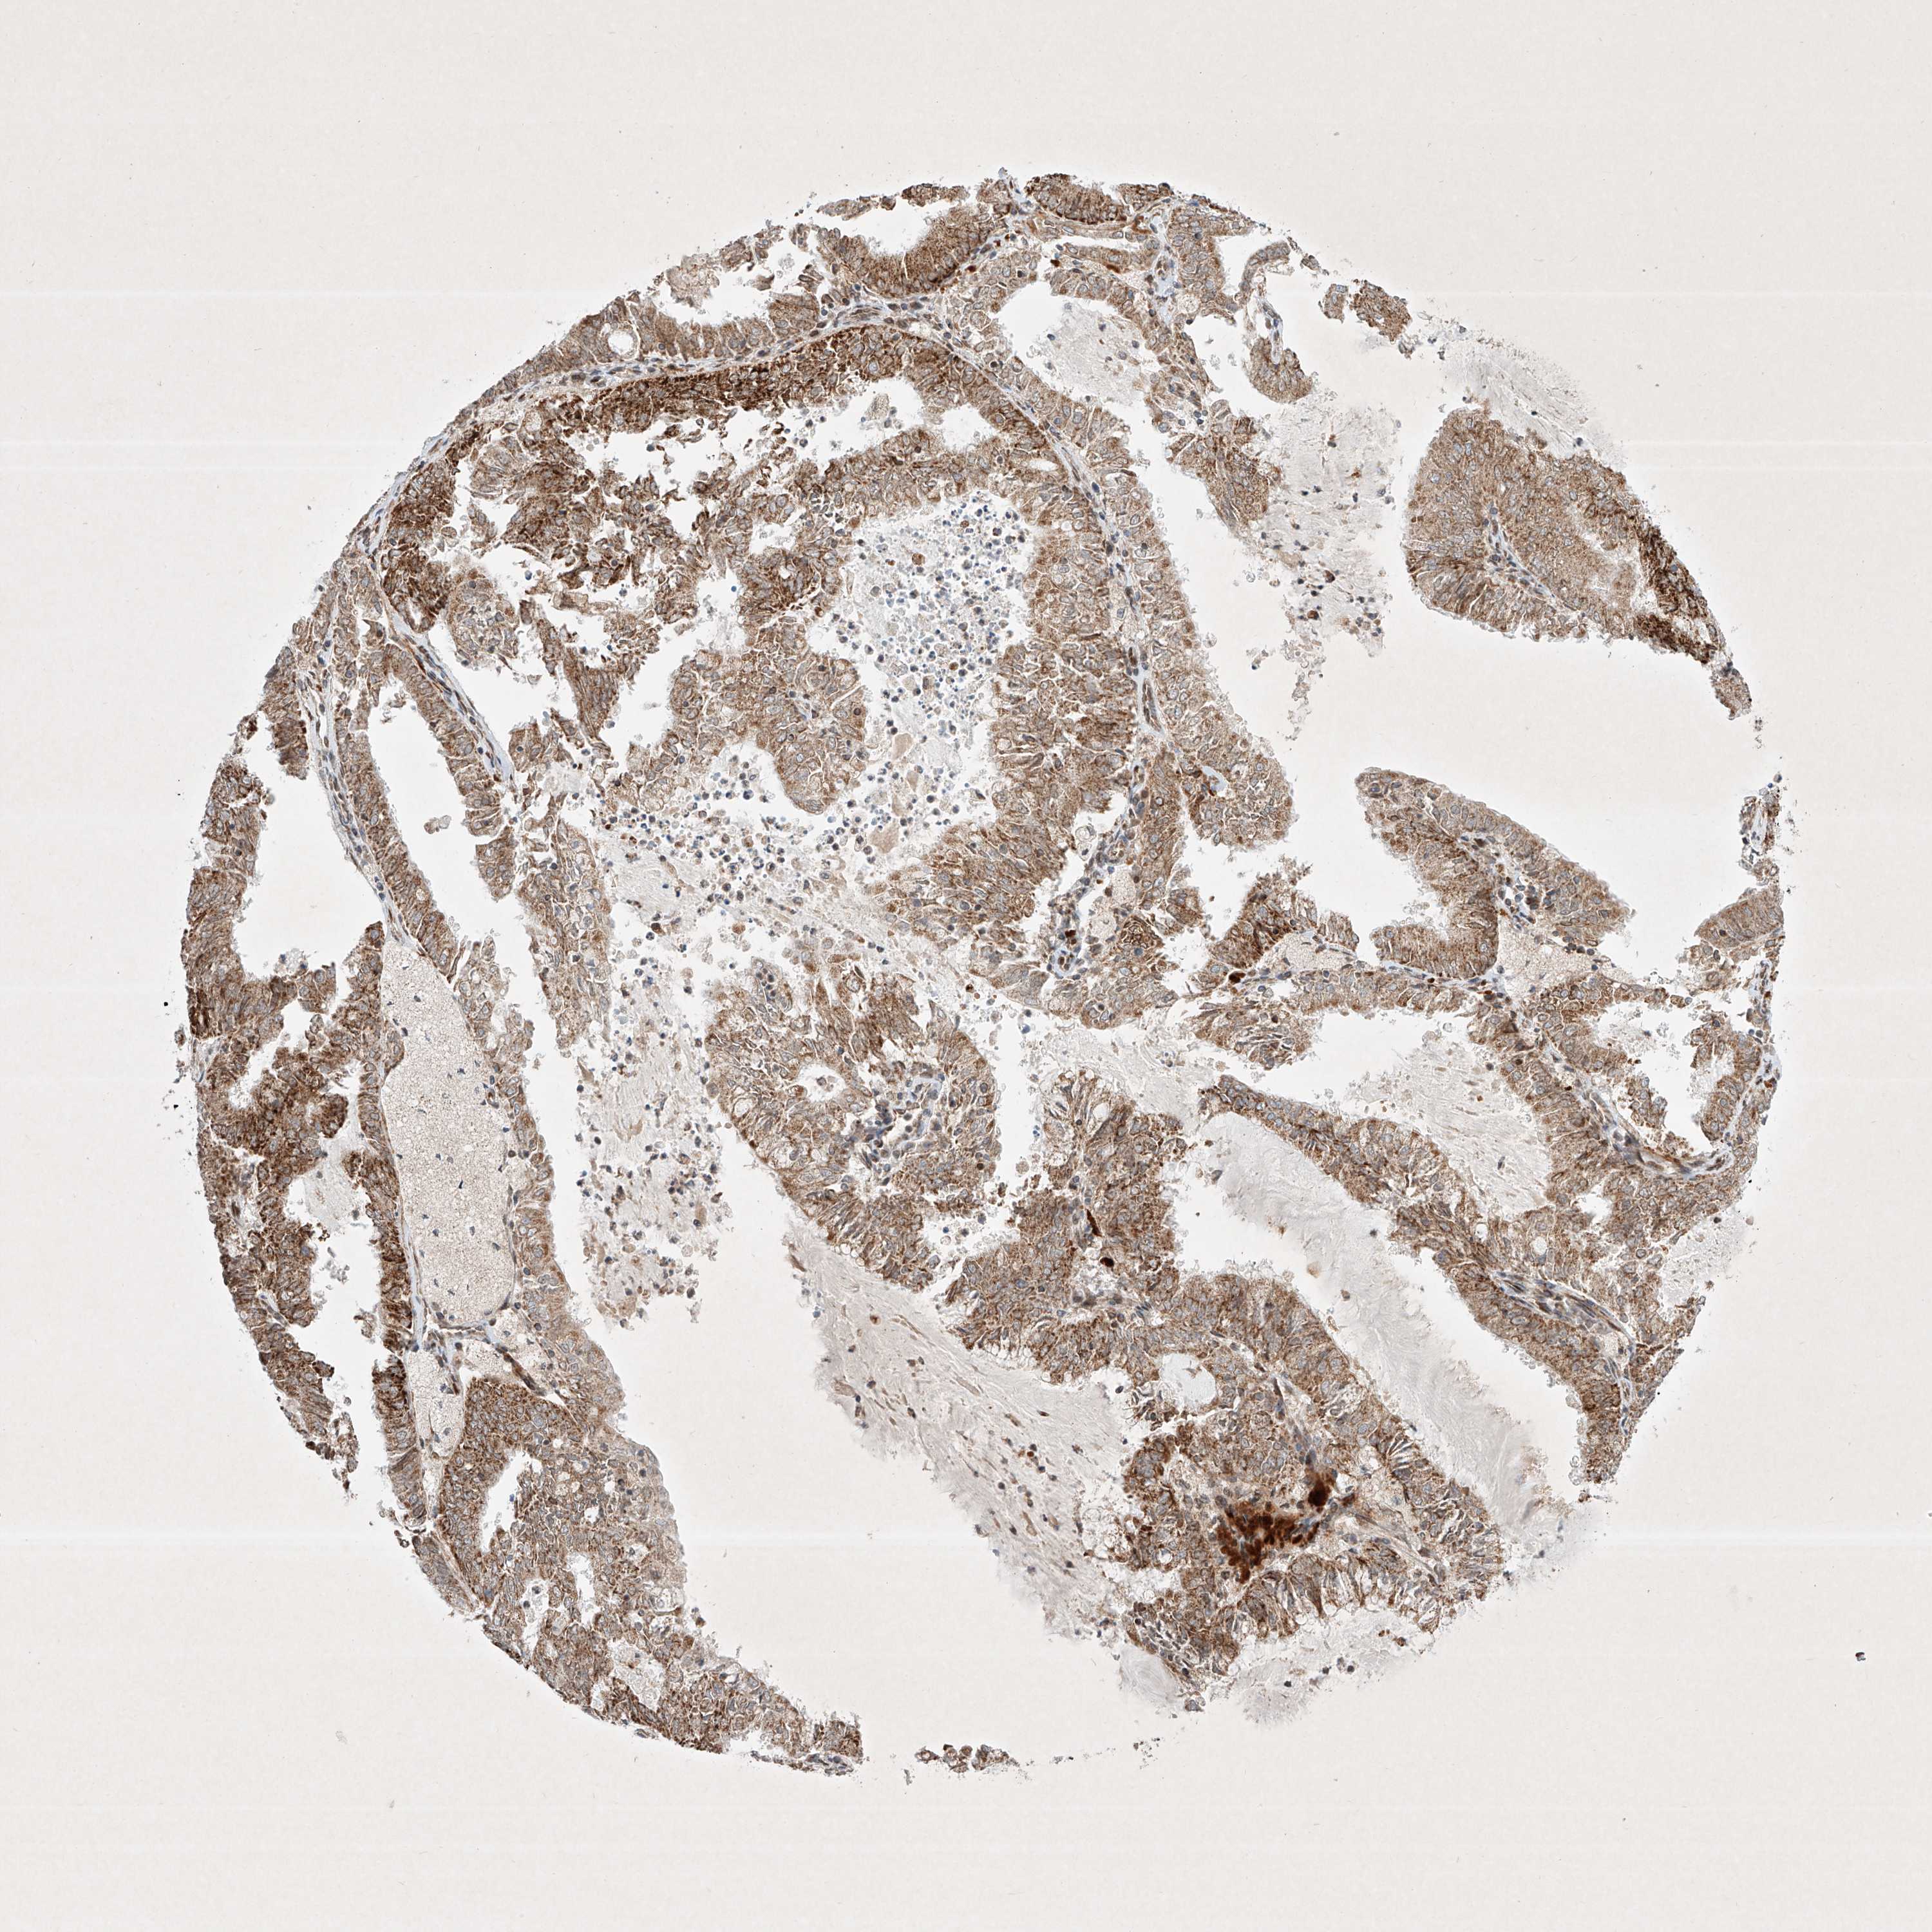

ENDOMETRIAL CANCER - Protein expressioni

A mouse-over function shows sample information and annotation data. Click on an image to view it in a full screen mode. Samples can be filtered based on level of antibody staining by selecting one or several of the following categories: high, medium, low and not detected. The assay and annotation is described here.

Note that samples used for immunohistochemistry by the Human Protein Atlas do not correspond to samples in the TCGA dataset.

Antibody stainingi

Antibody staining in the annotated cell types in the current human tissue is reported as not detected, low, medium, or high, based on conventional immunohistochemistry profiling in selected tissues. This score is based on the combination of the staining intensity and fraction of stained cells.

Each image is clickable and will lead to virtual microscopy that enables deeper exploration of all samples and also displays staining intensity scores, fraction scores and subcellular localization as well as patient and tissue information for each sample.

Antibody HPA031689

Staining

High

Medium

Low

Not detected

Intensity

Strong

Moderate

Weak

Negative

Quantity

>75%

75%-25%

<25%

None

Location

Nuclear

Cytoplasmic/membranous

Cytoplasmic/membranous,nuclear

Adenocarcinoma, NOS

Adenocarcinoma, metastatic, NOS